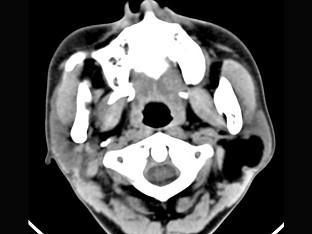

问题 男性38岁,左侧腮腺渐进性肿大一年,无压痛,CT扫描如图所示,请选择正确的描述和结论 ( )

选项 A、考虑为脂肪瘤 B、考虑为血管瘤 C、肿块边缘清楚,未见邻近结构受侵 D、考虑为囊肿 E、左侧腮腺区见低密度肿块,CT值约为-200Hu

答案 ACE